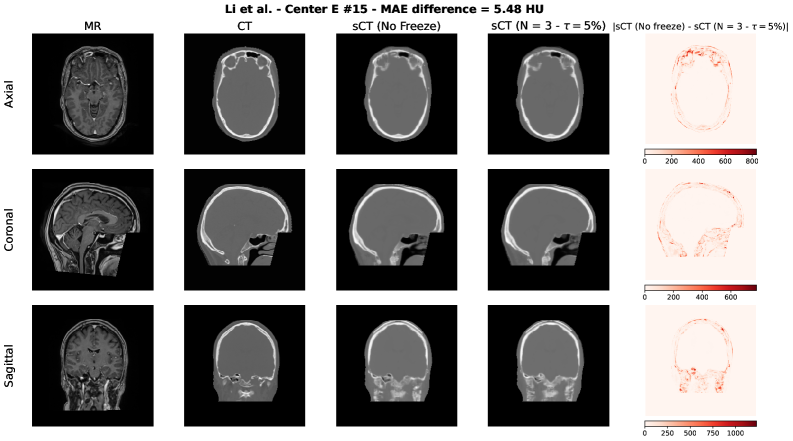

To qualitatively assess the potential impact of the adaptive freezing strategy on the generated synthetic CTs (sCTs), we conducted a visual comparison between the sCTs obtained with and without the proposed methodology. For each model employed in the study, we selected two representative test cases based on the following criteria:

• The case with the minimum difference in terms of MAE, thus the lowest difference between the sCTs MAE generated with and without adaptive freezing.

• The case with the maximum difference in terms of MAE, thus the highest difference between the sCTs MAE generated with and without adaptive freezing.

Each figure presents the following for the axial, coronal and sagittal plane of the central slice:

1. 1.

Input MR image;

2. 2.

Ground-truth CT image;

3. 3.

sCT generated without adaptive freezing;

4. 4.

sCT generated with the proposed adaptive freezing, using 𝒩=3\mathcal{N}=3 and τ=5%\tau=5\%;

5. 5.

Absolute difference map between the two sCTs.

Figure S4: Li et al. architecture [36] – Maximum MAE difference case.

Refer to caption

Across all models and both selected cases, no relevant and systematic structural differences were observed. The differences highlighted in the absolute difference maps and the variation in MAE are attributable to the stochastic nature of the training process (e.g., batch shuffling and optimization path variability) rather than the direct effect of the adaptive freezing mechanism.

This findings are aligned with the results observed in terms of MAE, PSNR and SSIM presented in this study.